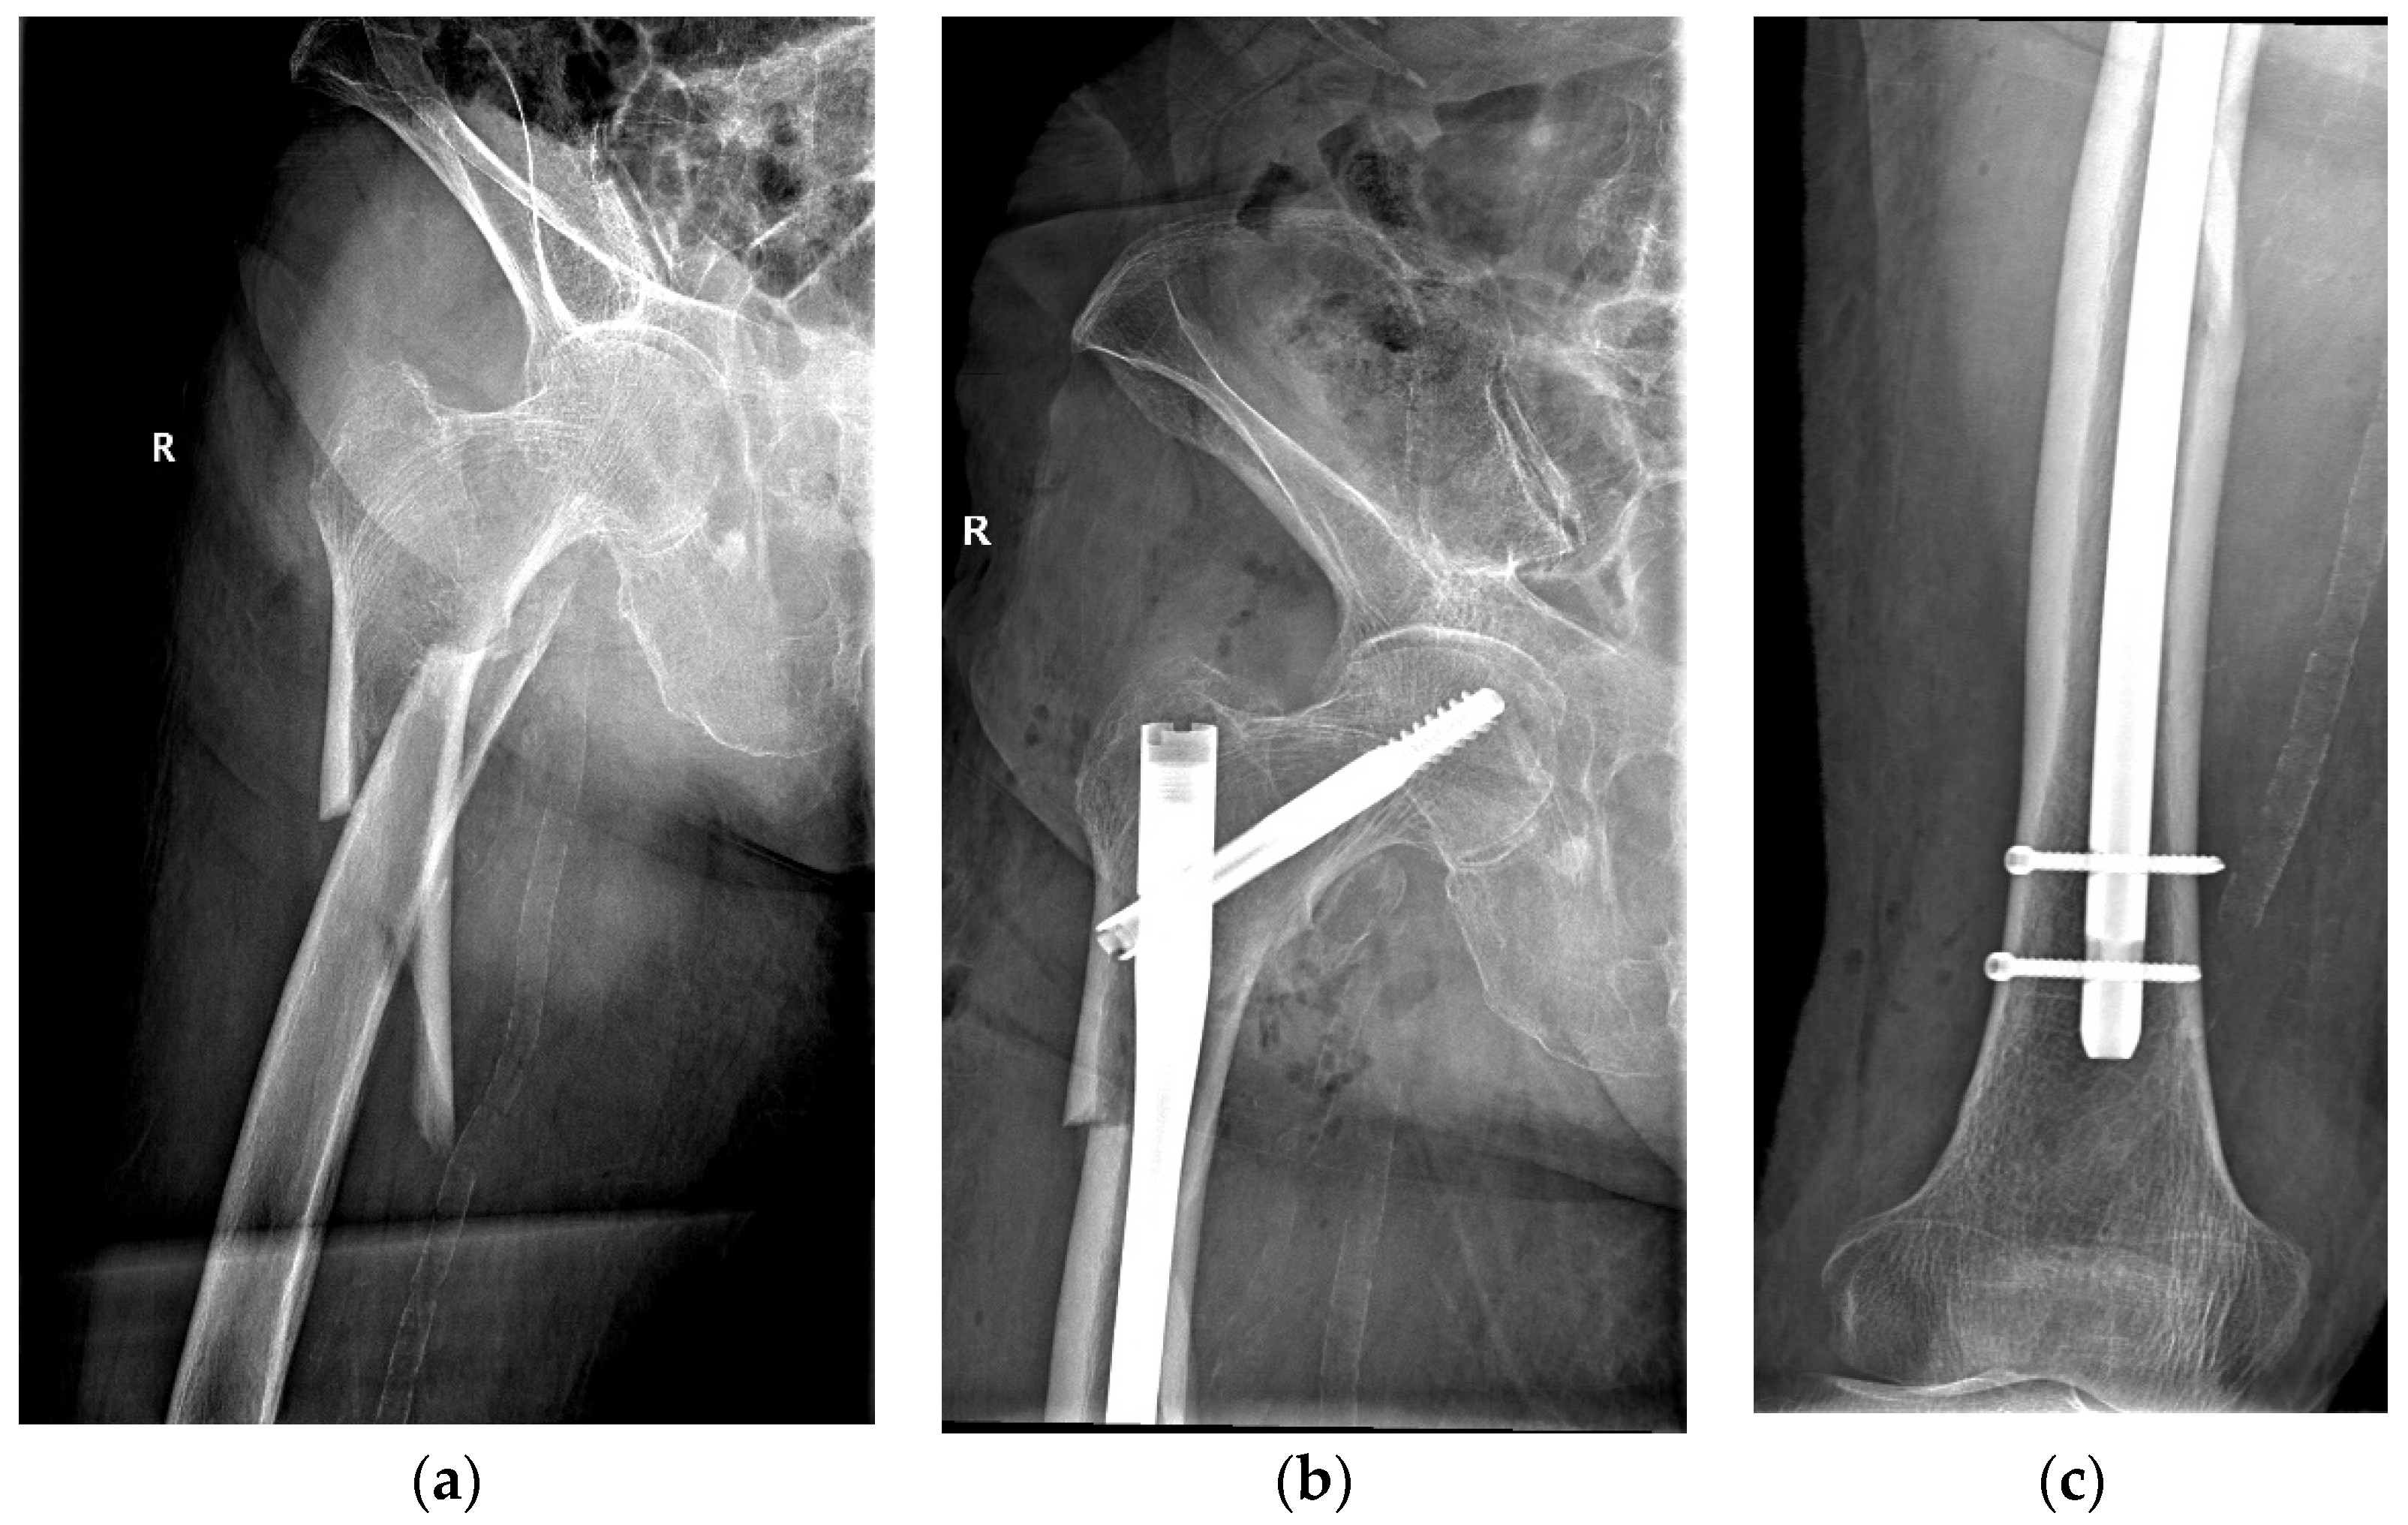

The same surgical technique was performed in all cases by experienced orthopedic surgeons from the department. Patients underwent spinal anesthesia (with 0.5% heavy Marcaine and Sufentanyl) or general anesthesia (with Ketamine and Esmeron) and were also given standard antibioprophylaxis (with Cefuroxime 1.5 g for three days). The long Stryker Gamma3 Nailing System (Stryker Corp., Kalamazoo, MI, USA) was used for the internal fixation under intraoperative fluoroscopy. A dedicated orthopedic table provided closed fracture reduction with an estimated length of incision of 4 to 5 cm, although conversion to open reduction was needed in more demanding cases. Figure 2 shows the pre- and postoperative radiographs of a representative case.

Figure 2.

An 84-year-old patient diagnosed with a subtrochanteric fracture after a fall from the same height treated with CRIF with long Gamma Nail fixation: (a) preoperative radiograph; (b,c) postoperative radiographs.